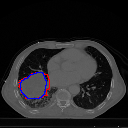

A qualitative analysis of our results reveals the strengths and weaknesses of our proposed model. In most cases, regardless of the size of the ground truth, our model predicts the tumor shapes very well. This is evident from Figure 4 where the ground truth and the prediction (by Deeply Supervised MultiResUNet) are shown in red and blue respectively. Although the tumors are in various arbitrary locations within the lung and appear in diverse sizes, the red and blue margins appear to coincide almost perfectly.

Figure 5 shows a comparison between predictions by the MultiResUNet model and Deeply supervised MultiResUNet model. It can be seen that the latter can delineate the tumor edges more accurately than the former. The ground truth (shown in red) and the prediction (shown in blue) have a more consistent alignment with each other in Deeply Supervised MultiResUNet’s prediction.